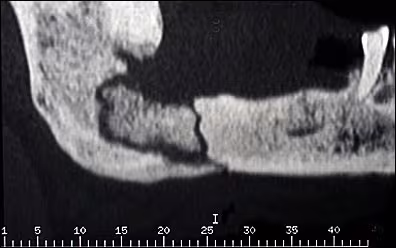

The latter was confirmed with a CT-scan sagittal image (Figure 4). The CT scan also clearly demonstrated a large bony sequestrum undergoing resorption surrounded by the irregular radiolucency. Both radiographs showed evidence of sclerotic bone surrounding the lesion.

Figure 4. A CT-scan (sagittal view) of the right posterior mandible demonstrating a large and irregular bony sequestrum, pathologic fracture, and sclerosis of the bone surrounding the lesion.